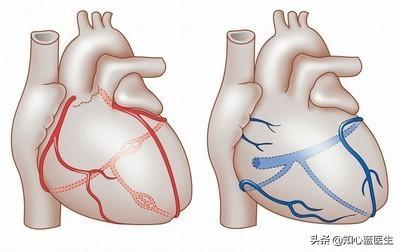

(1) 冠動脈:冠動脈は心臓、すなわち心筋そのものに血液を供給する動脈である。 冠動脈には3本の太い幹があり、それが次第にさまざまな枝に漸増し、最終的には心臓と心筋組織全体に密な魚網を形成する。冠動脈疾患病変の大部分はこの3本の太い幹にあり、枝分かれの第一段階である小枝の病変は比較的小さい。臨床用語で "3枝病変 "とは、右冠動脈、前下行枝、エコー源性枝の3つの主幹を指す。

- 冠動脈は、心臓そのものに血液を供給する動脈であり、動脈硬化、または私たちがよく呼ぶプラークである。冠動脈はプラークを生成し、プラークは徐々に大きくなり、心臓への血液と酸素が不足し、さまざまな症状を引き起こす。

冠動脈性心疾患とは、冠動脈アテローム性動脈硬化性心疾患の略称であり、主に心臓に血液を供給する動脈である冠動脈のアテローム性動脈硬化によって引き起こされる。動脈にアテローム性動脈硬化症が起こると、動脈の内表面にプラークが形成され、プラークが蓄積するほど動脈の直径が狭くなる。狭窄の程度が50%未満であれば、心筋への血液供給には影響しないので、一般的に症状はありませんが、50%以上になると、心筋への血液供給に影響を及ぼし、心筋の酸素消費量が増加しても、心筋が十分な酸素を得ることができず、心筋虚血、低酸素状態になると、胸部圧迫感、胸痛の症状が誘発され、これを狭心症と呼びますが、狭心症の症状は活動を停止すると徐々に緩和されます。狭窄の程度がさらに悪化したり、局所的なプラークの破裂、冠動脈の血栓閉塞によって心筋虚血が生じたりすると、狭心症の程度はさらに悪化し、緩和されない状態が続き、閉塞が解除されなければ心筋虚血壊死を引き起こし、ついには患者の突然死に至ることもあり、これが心筋梗塞と呼ばれるものです!